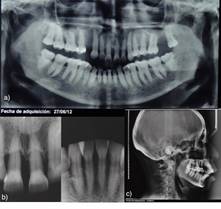

Análisis radiográfico: En las radiografías panorámica y periapical de sextante 2 y 5 se observa en el maxilar reabsorción ósea marginal horizontal discreta a marcada generalizada, avanzada en dientes 1.1 y 2.1, en mandíbula se observa reabsorción marginal horizontal discreta generalizada, marcada en incisivos (Figura 3a y 3b).

Diagnóstico: Paciente con periodontitis etapa III generalizada grado B. Tiene MDP en sextante 2 y 5, proinclinación de dientes 1.1 y 2.1, con presencia de diastemas y extrusión de diente 1.1. Clase II esqueletal, braquifacial, desdentada parcial, ausencia de dientes 1.4 y 2.7, protrusión y proinclinación incisiva (Figura 3c). Neutroclusión canina derecha, mesioclusión canina izquierda, mesioclusión molar bilateral, overjet 3mm. y overbite 5mm.